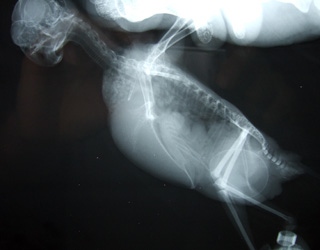

先ずは、衝撃写真 から…

07-11-17poria2.jpg

ポリアの正真正銘ヌードです( ̄□ ̄;)

お尻の所に、不審な物が…

こ、これは~卵?

どうもかなり大きな卵で、自分で産めそうにないので

産道を広げて押し出すことになりました

先生とパパとママの三人掛りで保定して、

押すこと15分…

やっと産まれました~\(^ ^)/